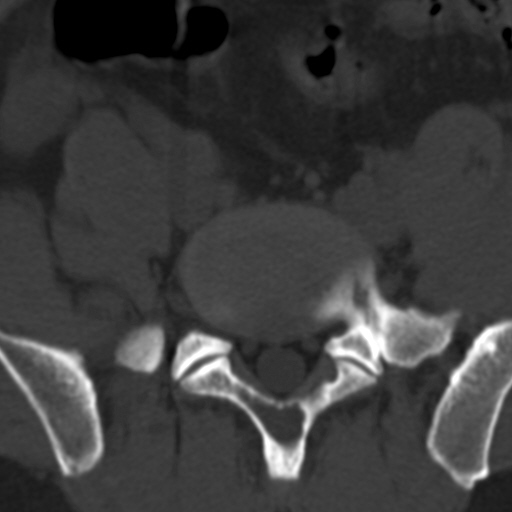

标题: CT4742:椎弓病变,请各位会诊。

男性,37岁,体检发现。

椎弓棘突形态、大小正常,左右椎板及棘突交界区骨质缺损,考虑良性病变(血管瘤可能)。

椎弓棘突形态、大小正常,左右椎板及棘突交界区骨质缺损,边缘清楚,后分见两个小点状高密影,考虑良性病变[血管瘤、成骨细胞瘤,骨纤,骨囊肿]

左右椎板及棘突交界区骨质缺损,周围未见软组织肿块及肿胀,考虑良性病变(血管瘤可能)。

破坏区呈彭胀性 切有硬化缘 考虑良性占位  囊肿可能性大